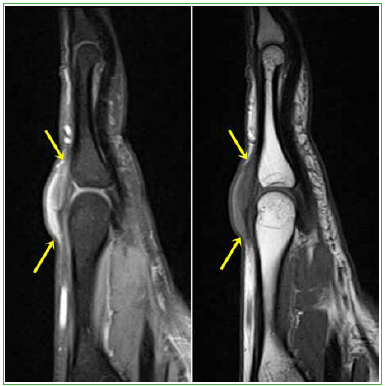

El examen de las otras regiones también mostró tumoraciones fusiformes en los tendones extensores del tercer dedo (Figuras 5 y 6) y el tríceps (Figuras 7 y 8), en forma bilateral.

Figura 6. Resonancia

magnética, corte sagital

potenciado en densidad

protónica con supresión grasa

(2100/25) y T1 (587/13)

de la mano derecha.

En el plano sagital, el nódulo

(flechas amarillas) adquiere una

morfología fusiforme.